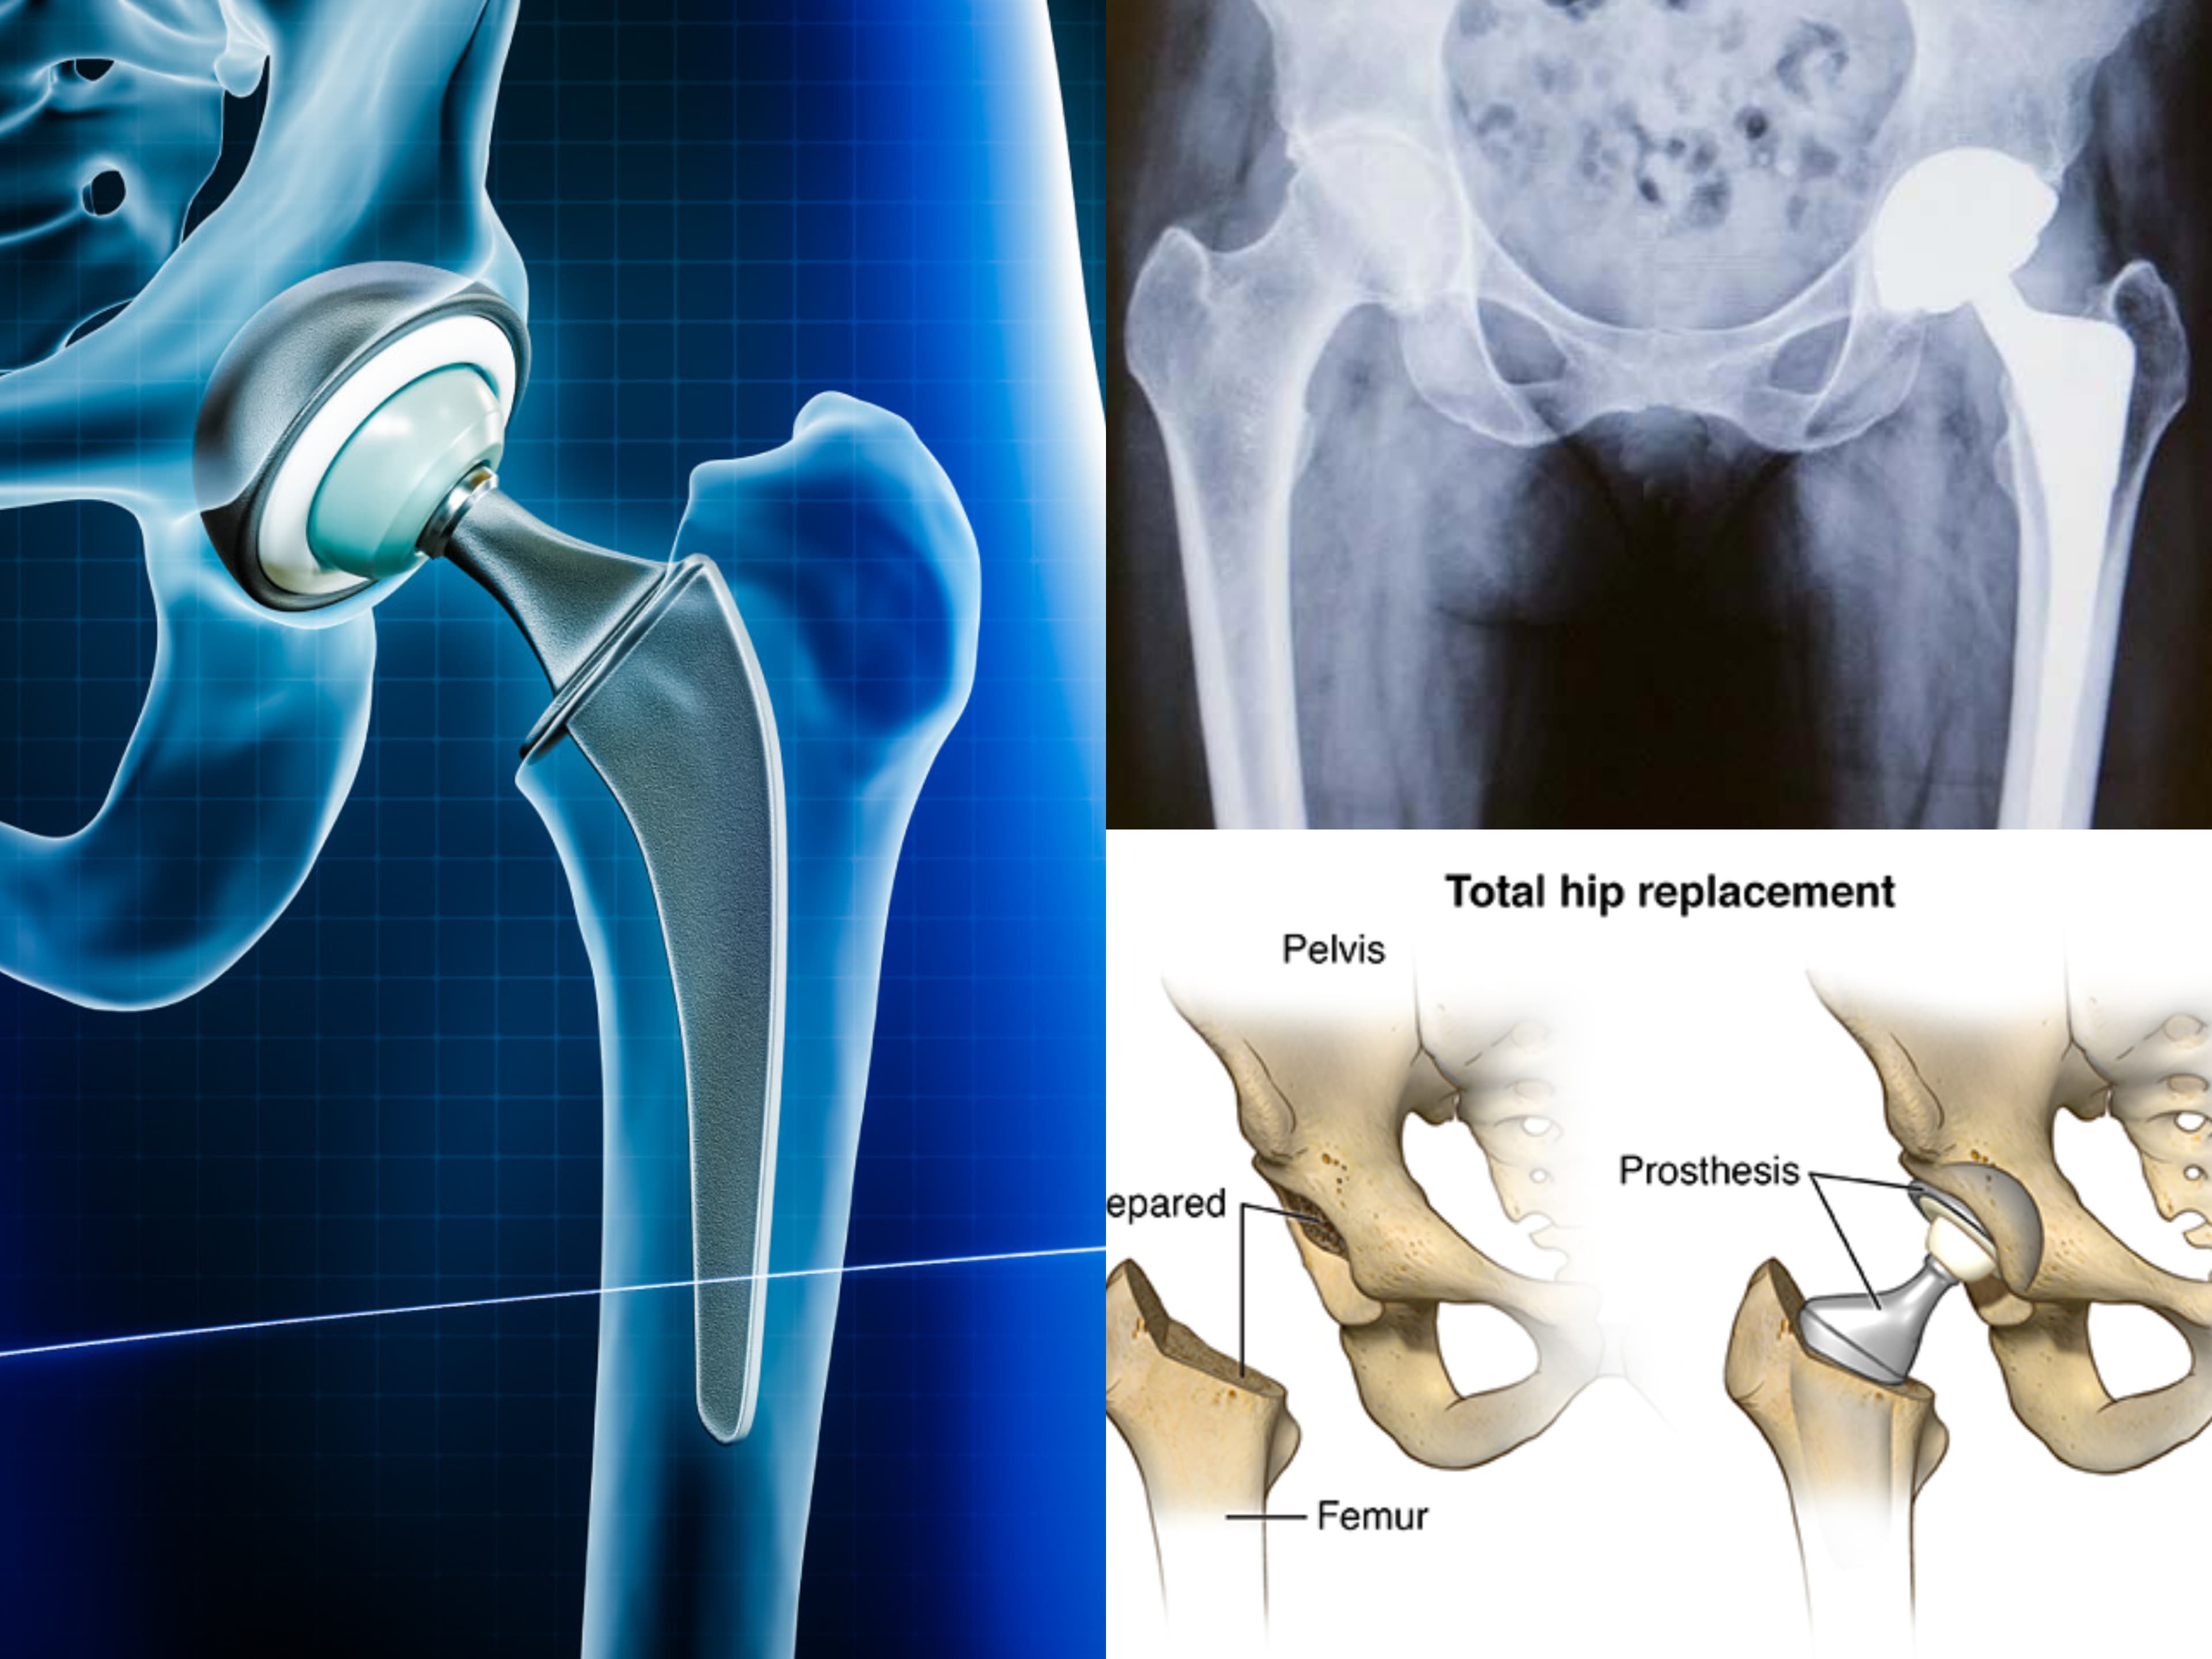

Many users have shared their positive experiences of successful surgeries, such as ACL keyhole surgery, hip replacement, and knee replacement surgeries. The staff is helpful and courteous in assisting patients with formalities and appointments.